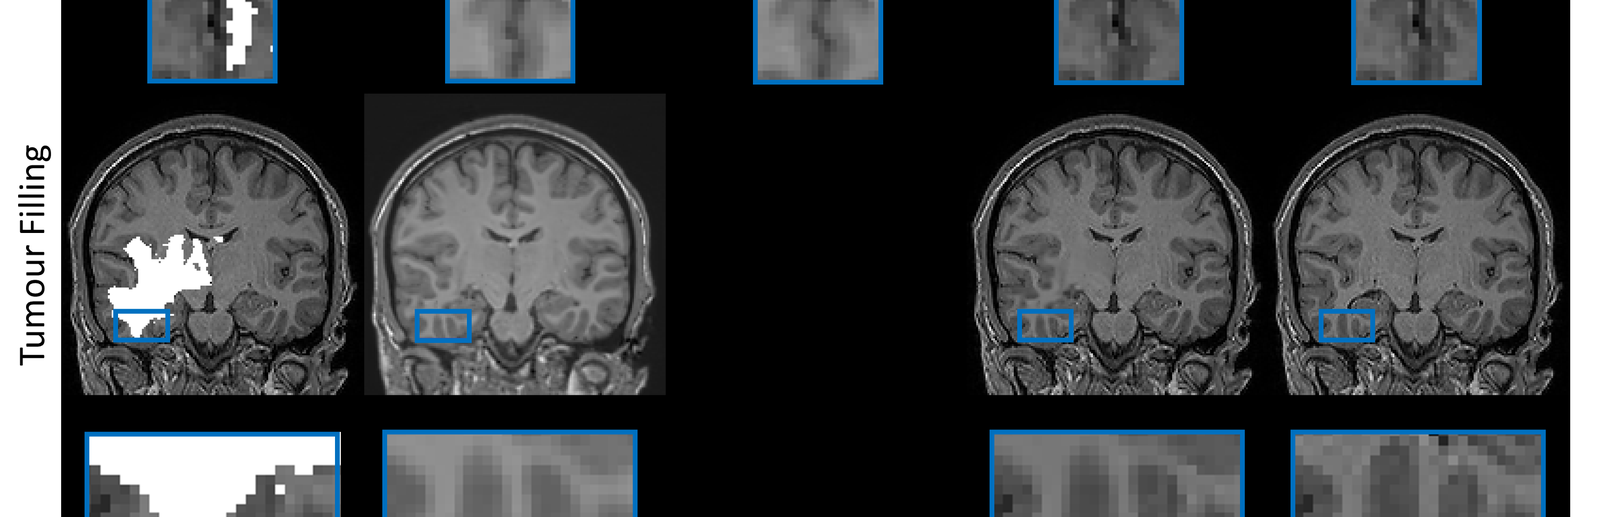

During my PostDoc in Polina Golland’s lab at MIT, I worked on machine learning algorithms for healthcare applications. I developed generative models for natural images, Chest X-Rays and brain images, which can be used as prior models for image reconstruction tasks, using bayesian posterior optimisation.

Using ML and compressed sensing techniques to improve the quality, speed and cost of medical scans.

Develop models for generation, reconstruction and manipulation of images, text or other high-dimensional data.